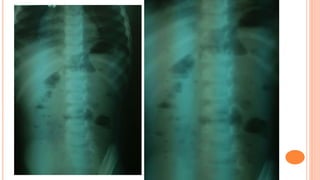

FECAL RETENTION IN

CONSTIPATION CASE

11 year old female comes to the clinic presenting

with a chief complaint of abdominal pain. The

abdominal pain is generalized in location, and

described as a dull pain, non-radiating. She

notes some acid reflex, and reports she has a

history of gastritis. She also notes decreased

appetite recently. Denies any nausea or

vomiting, denies any recent bowel changes.

Physical Exam: Unremarkable except some

generalized tenderness in the abdominal region,

no rebound, no guarding.

The abdominal x-ray shows evidence of duodenal

obstruction with a paucity of bowel gas through the

rest of the abdomen